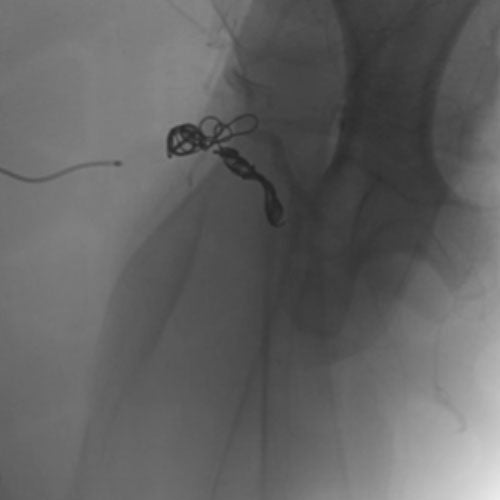

Ruby Standard Coil shown in iliac right artery Ruby Standard Coil shown in right internal iliac artery

Right Internal Iliac Artery

5 Ruby Standard 6x20

Embold Fibered Coil shown in left internal iliac artery Embold Fibered Coil shown in left internal iliac artery

Left Internal Iliac Artery

3 Embold Fibered Coil 6x20